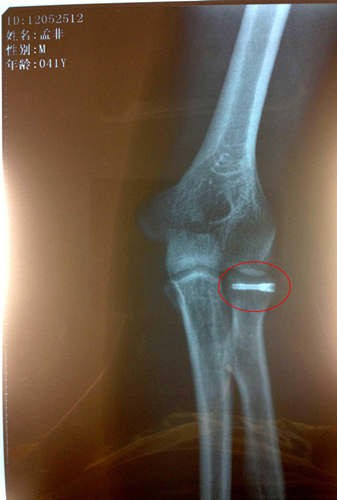

孟非打鋼釘x光片

自孟非不慎跌落舞臺之后,他的傷情也是牽動了無數(shù)人的心。據(jù)悉,在孟非回到南京后立即接受了手術(shù)且手術(shù)進行地非常成功,術(shù)后一直在家中休養(yǎng)。最近傷勢恢復(fù)地很好,已經(jīng)不再用石膏和繃帶固定了,而是改成了鈦合金鋼釘固定,上周日“孟非粉絲團”的微博也首度曝光了孟非打著鋼釘?shù)腦光片。根據(jù)目前的情況,醫(yī)生預(yù)計傷愈時間會大大縮短。根據(jù)最近錄制計劃,本周末《非誠勿擾》恢復(fù)錄制,打著鋼釘?shù)拿戏且灿诮袢罩鼗毓ぷ鲘徫?,而對于孟非本周打著鋼釘回歸錄制,很多人則大贊勞模孟非是“主持人界的鋼鐵俠”

據(jù)了解,確診撓骨骨折的孟非在家中休養(yǎng)已經(jīng)有半個月時間,專心養(yǎng)傷術(shù)后恢復(fù)情況很好,孟非在家每天要保證一定時間的康復(fù)訓(xùn)練,在家全身心的養(yǎng)傷給了他最大程度的休息,接受手術(shù)的左手手臂已不用打著厚厚的石膏,不用吊著繃帶固定,孟非還開玩笑:“現(xiàn)在的醫(yī)療技術(shù)很先進,傷口處打上了一根鈦合金的鋼釘,就這樣一處理,然后就不用繃帶石膏里一層外一層的包了?!笔軅诩业拿戏且搽y得偷閑,陪陪家人,看看書,溜溜狗。